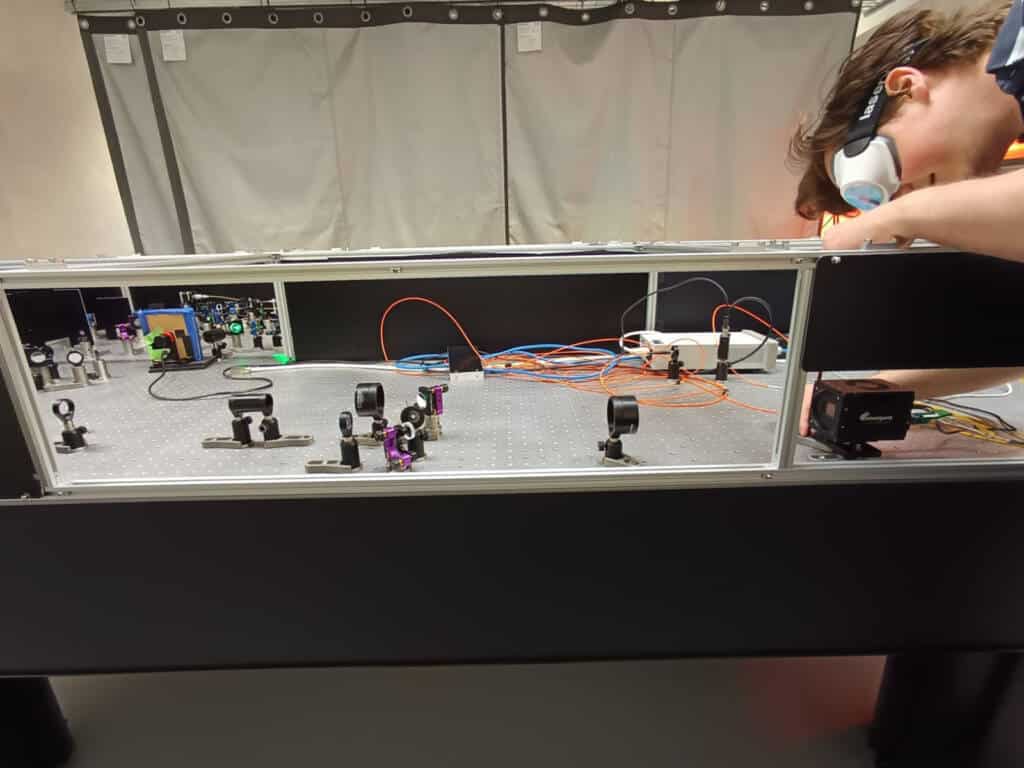

Daan Wolters adjusts the Emergent HZ-21000-G 100GigE high-speed camera that is fundamental to the lab’s work with phototransient holography.

Dennis van de Lockand (left) and Daan Wolters, who work on the phototransient holographic imaging research.